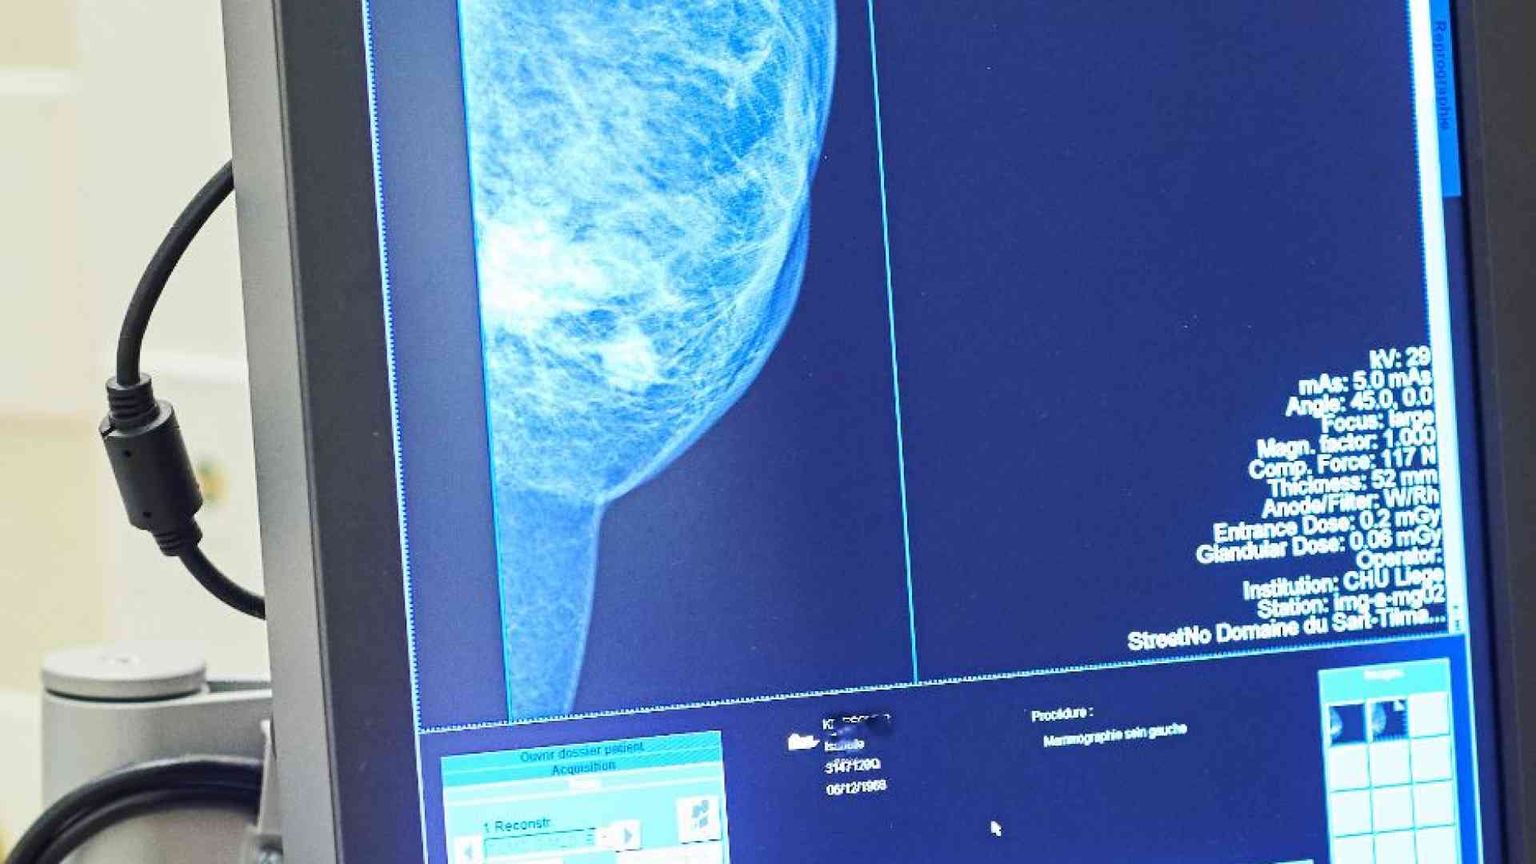

Significativa è l’attenzione alla prevenzione oncologica, specialmente per i tumori della mammella e dell’ovaio per le donne a rischio genetico per la presenza di varianti patogene dei geni Brca1 e Brca2. Il programma di screening prevede la ricerca delle varianti maligne nelle donne parenti di primo grado di chi è risultata affetta dalla patologia. Per chi risulta positiva ma sana, c’è un percorso di sorveglianza attiva finalizzato alla diagnosi precoce con visite senologiche, mammografie, ecografie, risonanze e consulenze oncologiche e ginecologiche.